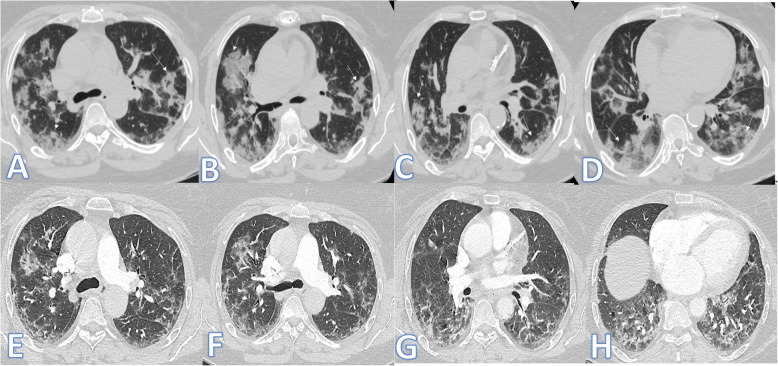

Fig. 1.

Fifty-five-year-old female: she has DM, HTN, and IHD; peak CT severity score 12; consolidation/crazy-paving score 10. She was admitted to the ICU; laboratory results show lymphopenia, high CRP, d-dimer, serum ferritin, and high-sensitivity troponin. Steroid was given; length of stay during hospitalization is 15 days. Peak CT during admission (a–d) showed bilateral consolidation patches more at the lower lobes with a crazy-paving appearance (arrows). Follow-up CT 3 weeks after discharge (e–h) shows lung fibrosis with a coarse reticular pattern mainly dependent (arrows).